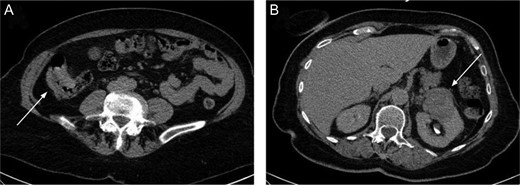

The present case is of a 70-year-old female patient with positive family history of leukaemia, colon cancer and type 2 diabetes mellitus. In the annual breast cancer screening, the mammography revealed a 1.7 cm × 2.5 cm mass in the upper outer quadrant of her left breast with axillary lymph node metastasis. Core biopsy confirmed invasive breast carcinoma (IBC) with low-grade ductal carcinoma in situ (DCIS), oestrogen and progesterone receptors were both positive (ER 100%, Q-score 7–8, PR 70%, Q-score 3–4), Her2 was negative (Score 0) and Ki67 labelling index was 5%. During the staging period, positron emission tomography-computed tomography (PET-CT) scan was performed and it demonstrated an abnormal FDG uptake in the upper part of the left kidney and in the right colon too (Fig. 1). On colonoscopy, 7–8 polyps were detected and an endophytic tumour in the ascending colon. Biopsy of the latter mass revealed moderately differentiated mucinous adenocarcinoma. Computed tomography confirmed a 3.8 cm × 3.6 cm mass of the left kidney and a 5 cm mass in the right colon extending until the hepatic flexure. (Fig. 2) Percutaneous CT-guided fine needle aspiration of the left kidney showed renal cell carcinoma. The case was referred to the multidisciplinary oncological team.

The right colon mass (A) and the left kidney mass (B) on the CT scan.